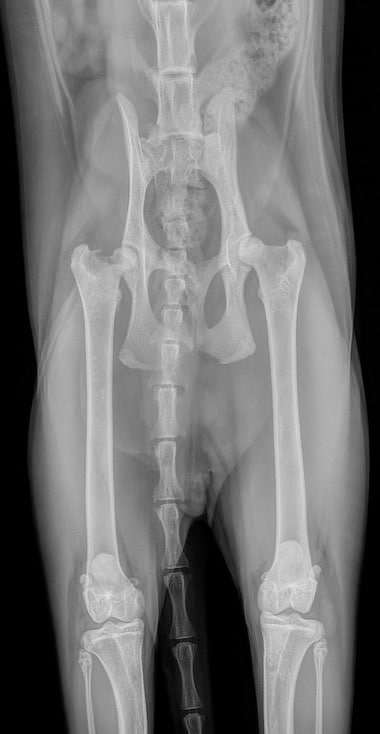

Nous avons effectué des radiographies du bassin et du fémur droit, qui ont révélé un glissement épiphysaire de la tête fémorale droite avec une sclérose osseuse sous-chondrale, ainsi qu’une dysplasie de la hanche gauche.

Les radiographies sont très souvent largement suffisante pour l’examen de la hanche, même si il faut parfois plusieurs incidences, en particulier lors de fracture.